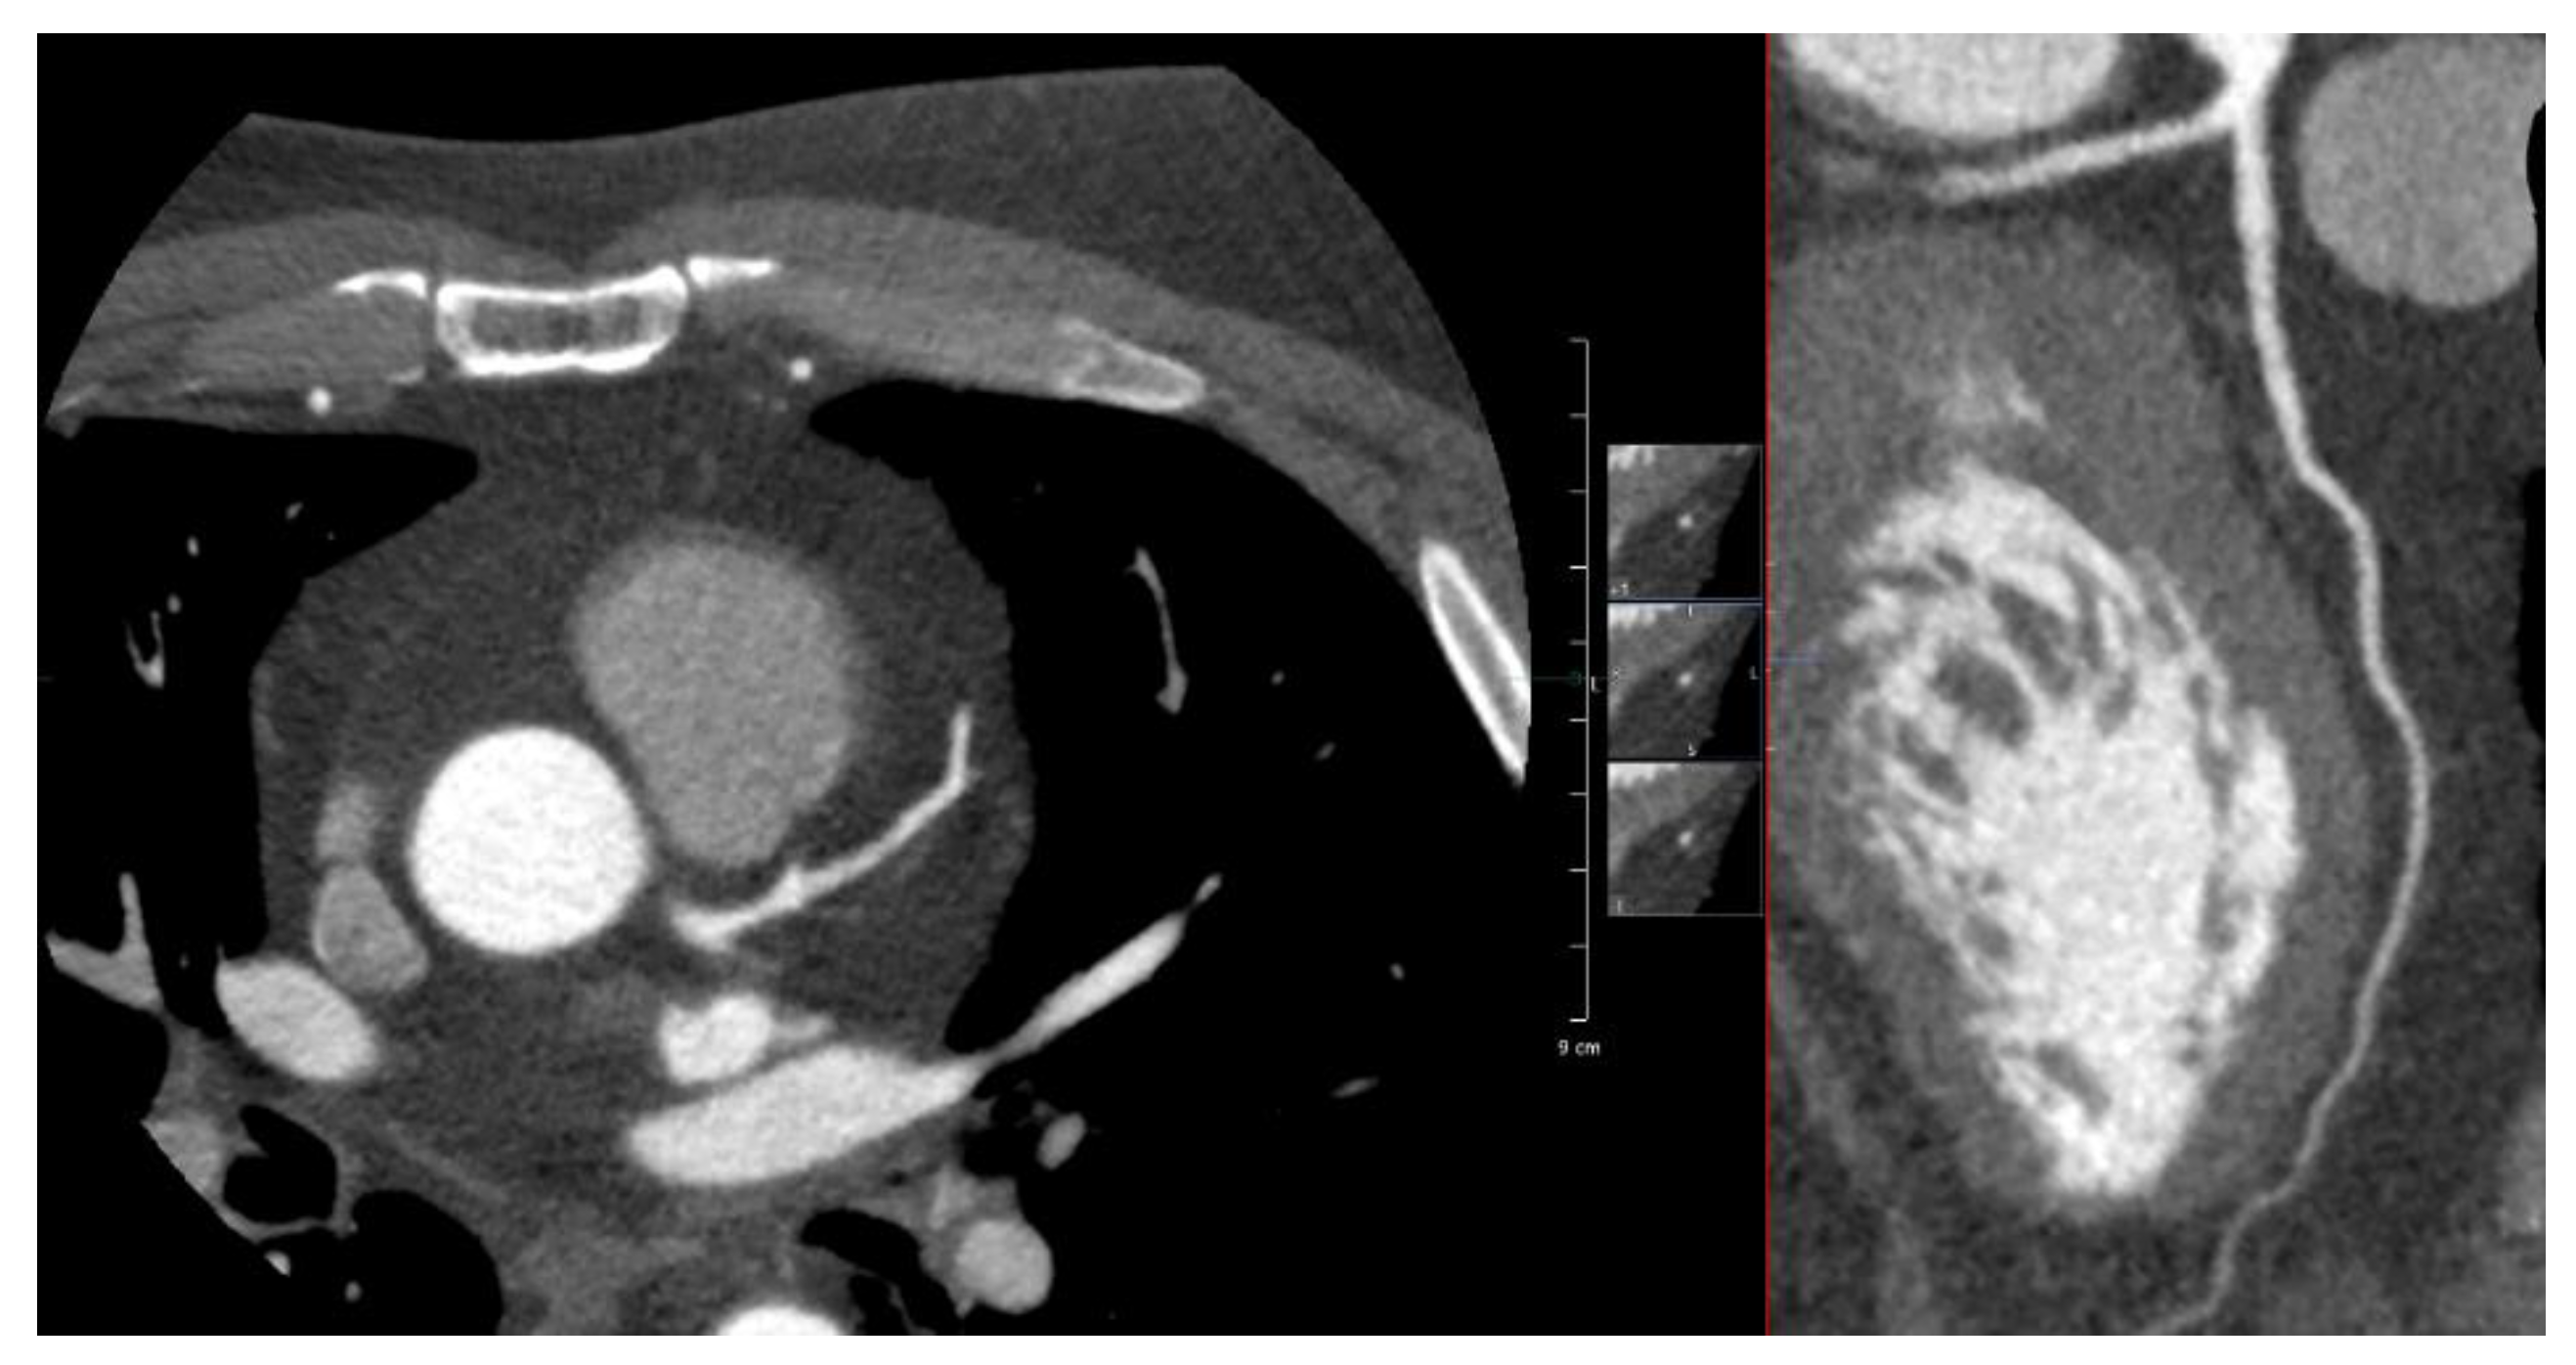

Appendix A.1. Patient A. Male, 46 Years

Appendix A.2. Patient B. Male, 45 Years